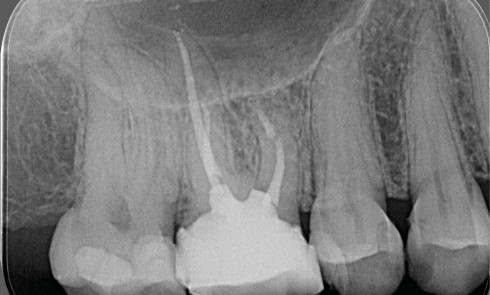

Endodontie

Article réservé à nos abonnés Les concepts actuels en microchirurgie endodontique

Les échecs endodontiques sont principalement causés par la persistance de micro-organismes au sein du système canalaire [1]. Le retraitement non...